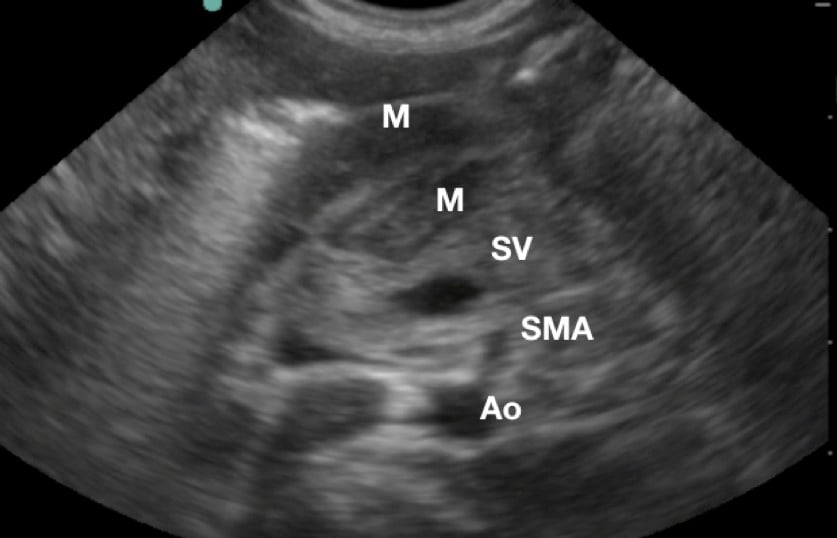

- Use the aorta/ superior mesenteric artery as additional landmarks if necessary (pylorus is anterior to them).

- Figure 3.Sonogaphic anatomy of the pyloric muscle (M) in relation to the aorta (Ao), superior mesenteric artery (SMA), and splenic vein (SV)